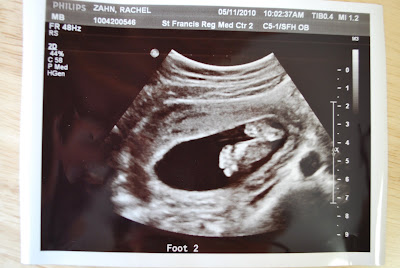

Our scanner is not working, so the pictures from the ultrasound I took with our camera. Ultrasound went well - took only about half an hour. Baby Z was kicking like crazy! Kicked the ultrasound wand several times. Must have been the orange juice I had this morning. Heartbeat was going about 157 bpm. The baby also wouldn't move it's head. The tech was trying to get a picture of the top of the baby's head for measuring purposes and it's head was tilted way back. The tech said baby's often find a position they like and don't move. The legs and arms were definitely moving though!

Feet. :)

The little kickers.